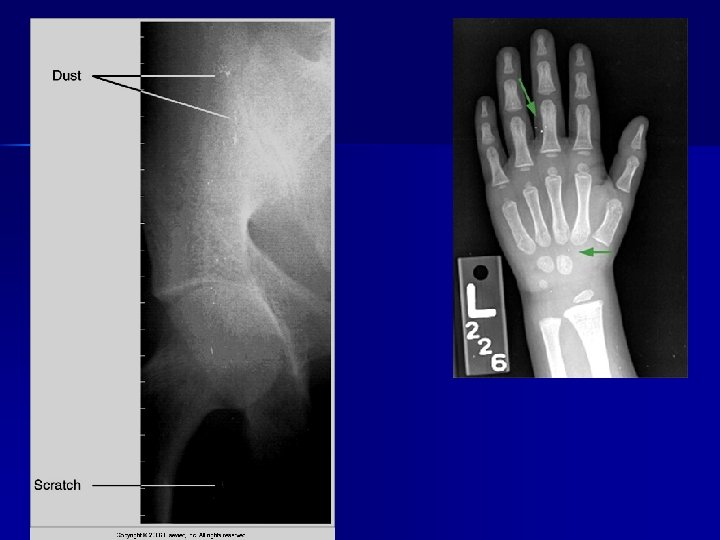

Artifacts - Types n Processing Artifacts n Exposure Artifacts n Handling & Storage Artifacts

Processing Artifacts Emulsion pickoff n Chemical fog n Guide-shoe marks n Water marks n Chemical spots n Guide-shoe & roller scratches n

Exposure Artifacts Motion n Improper patient position n Wrong screen-film match n Poor film/screen contact n Double exposure n Warped cassette n Improper grid position n

Artifact

Handling & Storage Artifacts Light fog n Radiation fog n Static n Kink marks n Scratches n Dirty cassettes n

Pt clothing

PATHOLOGY NOT ARTIFACT

Name & cause of this?

Evaluating Images What do you think?